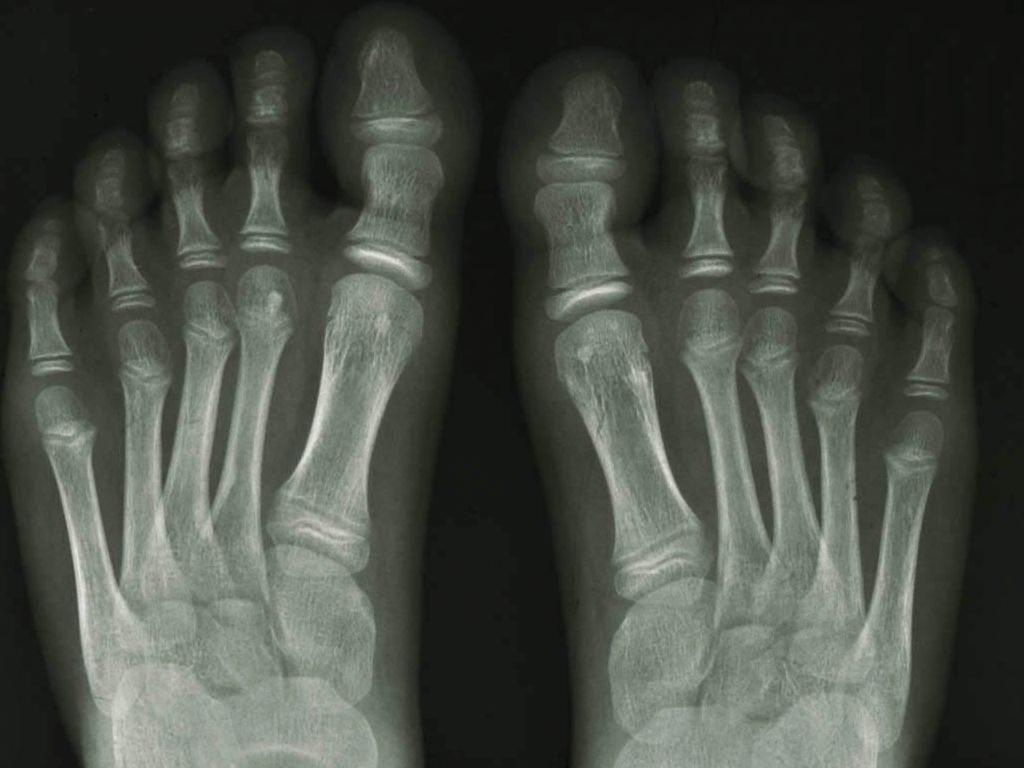

De osteopoikilosis

presenteert zich meestal vanaf 10 jaar. Meestal zijn er geen klachten maar wordt

het bij toeval op röntgenfoto’s ontdekt, of door gerichte diagnostiek bij een

positieve familieanamnese. Ongeveer 15% heeft pijnklachten. Op röntgenfoto’s

zijn symmetrisch verspreide, enkele mm tot 1 cm grote ronde of ovale sclerotische

haarden zichtbaar in epifysen en metafysen. Ze worden soms verward met osteoblastische

metastasen. Bij botscintigrafie niet aankleurend.

X-handen: Hellerhoff

- Wikimedia (Creative Commons License

3.0).